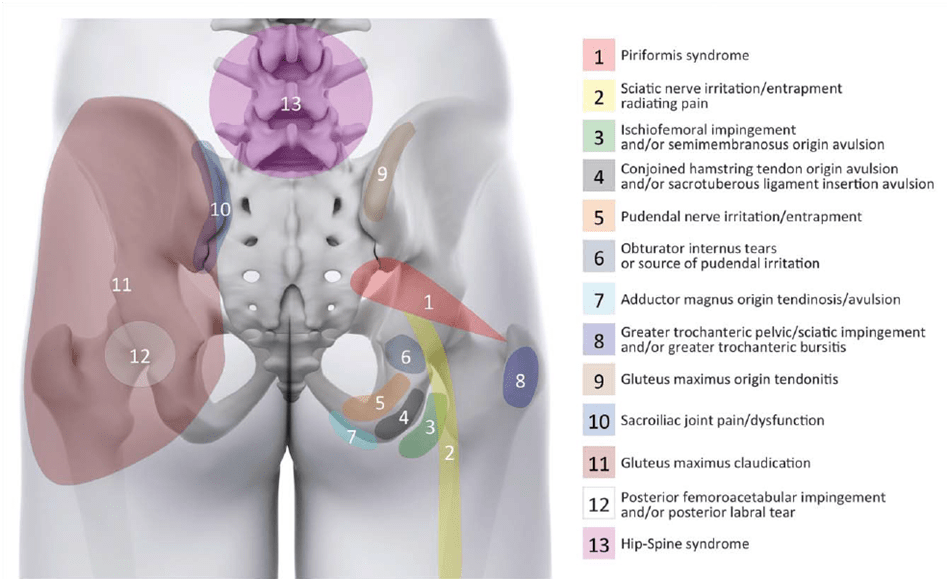

Om din patient bara rapporterar smärta i skinkan kan det finnas en mängd olika underliggande sjukdomar som gör det mycket svårt att ställa diagnos. Här är en översikt av Gomez-Hoyos et al. (2018) med möjliga bakomliggande orsaker till smärta i bakre delen av höften/skinkan:

Vår första prioritet är att undersöka ländryggen som ofta ger upphov till smärta i skinkområdet. Den sacroiliacala leden kan också vara en drivkraft för nociception. Klustret av Laslett kan vara till hjälp för att göra denna diagnos mer eller mindre sannolik. För de andra diagnoserna kan du hitta videor på vår kanal.